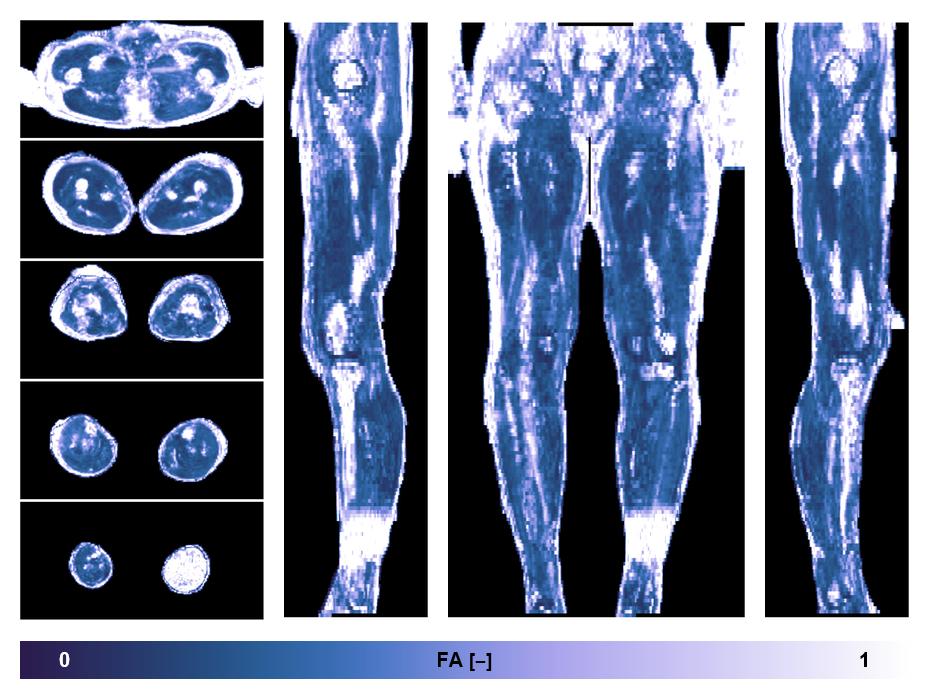

• Fractional anisotropy

IVIM corrected whole leg muscle fractional anisotropy obtained from diffusion tensor imaging.